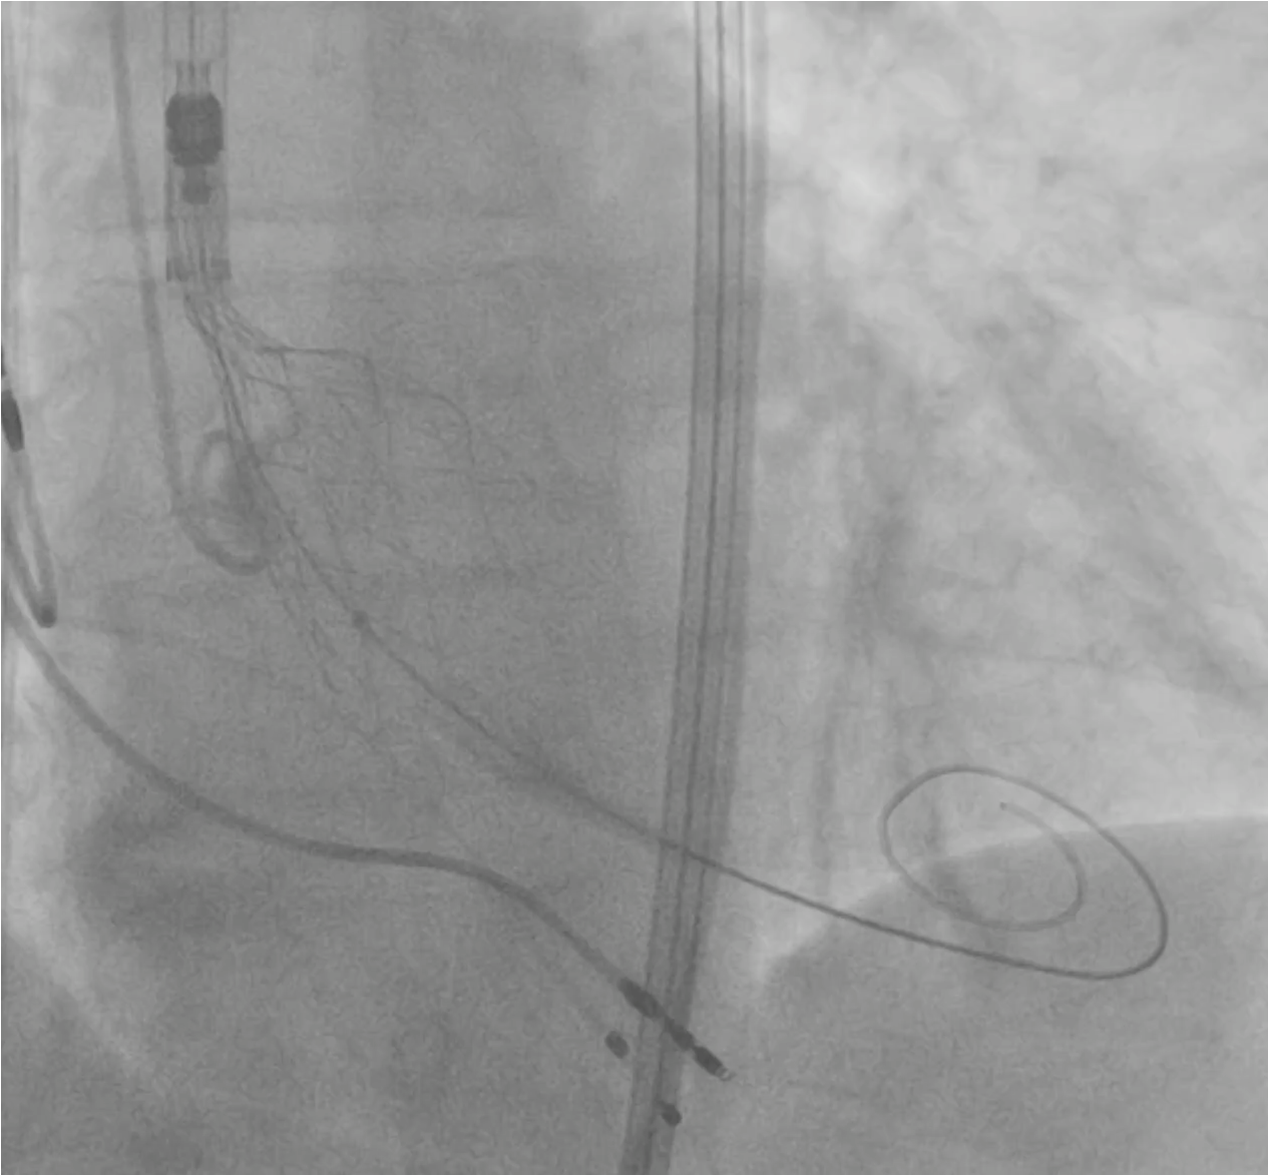

A super-rigid guidewire was inserted into the left ventricular cavity, and a valvulotomy was performed using a 23x40mm balloon catheter. After this, a successful implantation of a Portico 29mm aortic prosthesis was performed. During suturing of the access site, the patient developed persistent hypotension and bradycardia. A decision was made to perform catheterization of the left coronary artery trunk. During the angiogram, compression of the left coronary artery trunk by a hematoma in the projection of the fibrous ring was revealed. A decision was made to perform stenting of the left coronary artery trunk. The stent was successfully implanted in the left coronary artery trunk. Hemodynamics were restored. The patient was discharged on the 4th day after TAVI. A control MSCT was performed several months later.